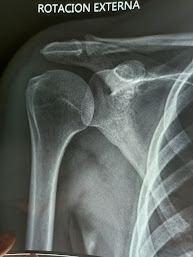

Ante la sospecha de una tendinitis calcificante del hombro, se realiza una radiografía para evaluar el tamaño de la calcificación y una resonancia magnética para descartar que exista una ruptura del tendon.